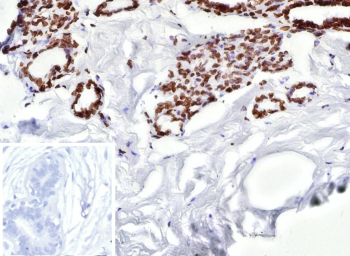

ER beta Antibody Breast Carcinoma IHC. Immunohistochemistry analysis of Estrogen receptor beta 2 in human breast carcinoma. Formalin-fixed, paraffin-embedded human breast carcinoma tissue was stained with ER beta/Estrogen receptor beta antibody (clone ESR2/9710), showing nuclear staining in tumor epithelial cells, with surrounding stromal cells largely negative. Hematoxylin was used as a nuclear counterstain. Inset shows a negative control section processed with PBS instead of the primary antibody, followed by secondary antibody only. Staining of formalin-fixed tissues required heating tissue sections in 10mM Tris with 1mM EDTA, pH 9.0, for 45 min at 95oC followed by cooling at room temperature.